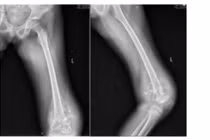

Phim chụp cho thấy khối u đã lan rộng toàn bộ khoang miệng, buộc phải cắt bỏ toàn bộ lưỡi, sàn miệng và nạo vét hạch cổ để loại bỏ tổn thương ung thư.

Bệnh nhi K.P.M., 10 tuổi, quê tại Điện Biên, người dân tộc Hà Nhì, nhập viện trong tình trạng sưng đau vùng đùi trái kéo dài, đi lại khó khăn. Qua thăm khám lâm sàng và thực hiện các xét nghiệm hình ảnh học, kết quả MRI cho thấy bệnh nhi M. có khối tổn thương kích thước 12x9cm ở đầu dưới xương đùi, ăn mòn vỏ xương, phá vỡ màng xương và lan vào phần mềm. Kết quả sinh thiết xác định bệnh nhi mắc osteosarcoma đầu dưới xương đùi trái– một thể ung thư xương ác tính thường gặp ở lứa tuổi thiếu niên.